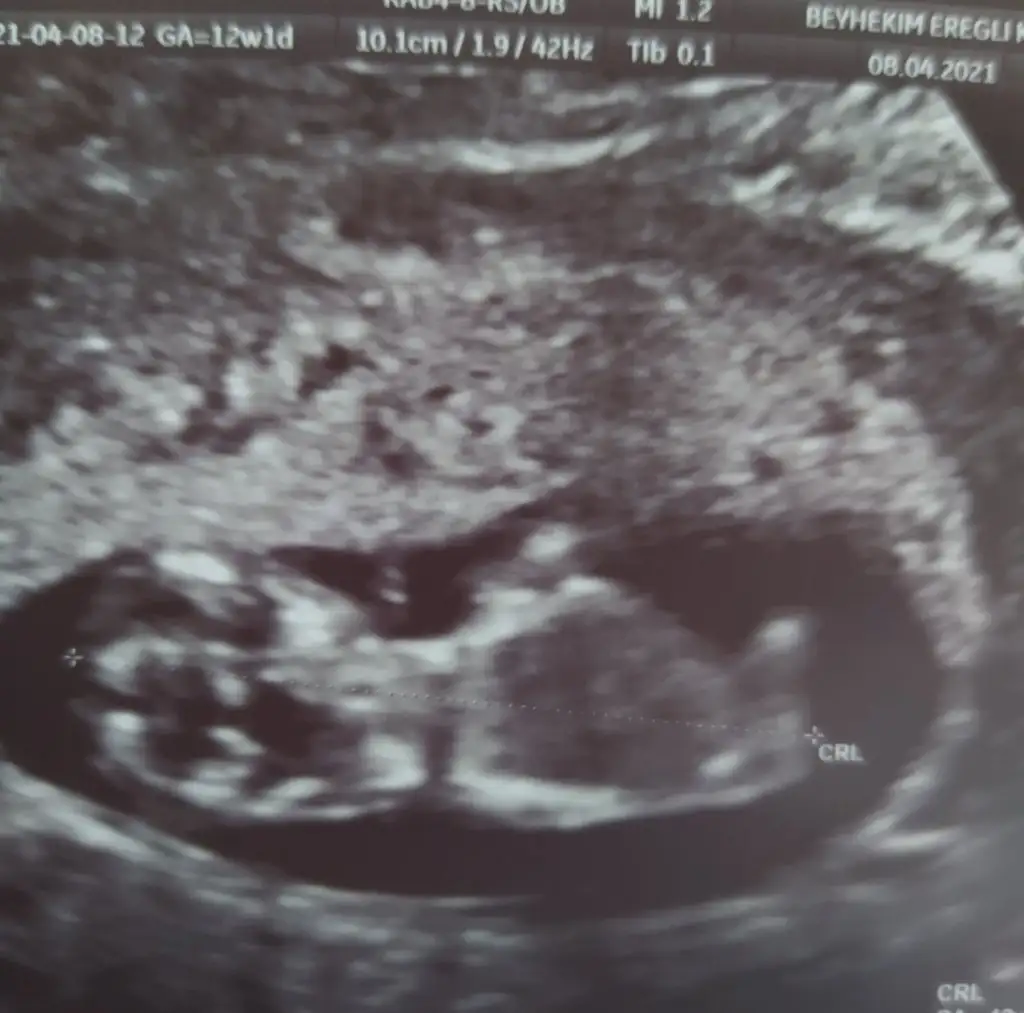

dr soylemeden siz gorun genital nub teorisi ( bebegin cinsiyeti)

Ikra meyra Ikra meyra canim 12+2 bı tahmin de bulunurmusun.İlk bebeğimi bilmistin ya.bunada yorum yaparsan sevinirim.tesekkurler .

Ikra meyra Ikra meyra 12+1 sata göre bana da bakar mısınız çok hareketli oldugu için bişey demedi Dr